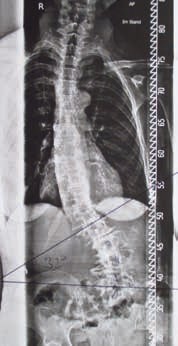

Die adulte Skoliose ist oft mit anderen Erkrankungen verbunden, die sich in der Beschwerdelage des Patienten durchaus als führend darstellen können. Krankheiten und Einschränkungen wie beispielsweise Parkinson, Osteoporose, Schrittmacher, Rollstühle oder Sondenzugänge erfordern individuelle Lösungen durch die Orthopädie-Technik, die sich meistens umsetzen lassen 9. Patienten mit einem Korrekturkorsett berichten von einer Entlastung oft nur beim Tragen des Korsetts während alltäglicher Tätigkeiten und auch nur stundenweise. Die Tragedauer ist grundsätzlich geringer als bei einer idiopathischen adoleszenten Skoliose, bei der das Korsett wachstumslenkend 23 Stunden pro Tag getragen werden muss. Ein begrenzender Umstand ist oft die schon sehr rigide Skoliose, die keine vollständige Korrektur mehr zulässt. Hier gilt es einen für den Patienten gangbaren Weg zu erarbeiten (Abb. 2a u. b).